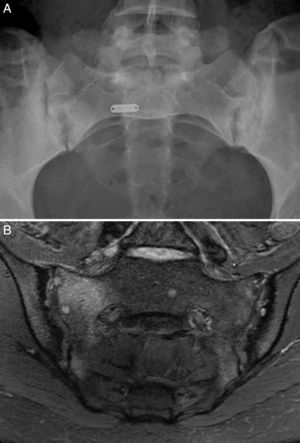

Caso 1: mujer de 28 años, con dolor lumbar crónico inflamatorio y astenia de 10 años de evolución. La radiografía simple mostró evidente sacroilitis bilateral. En la RM de sacroiliacas se objetivaron los siguientes signos de sacroilitis: esclerosis, erosiones y marcado edema óseo periarticular y bilateral (fig. 1). El HLA B27 fue positivo, de modo que el diagnóstico de espondilitis anquilosante quedó establecido. Tenía una hermana con EC. No tenía cuadro digestivo asociado. La serología de EC mediante el test de cribado de anticuerpos antitransglutaminasa y antipéptido deaminado de gliadina, tanto IgG como IgA, fue negativa. La tipificación HLA mostró DQ7 homocigoto, con ausencia de DQ2 y de DQ8. La biopsia duodenal mostró un infiltrado intraepitelial de 37 linfocitos CD3 por 100 enterocitos, sin atrofia de vellosidades. La mejoría del dolor lumbar y la astenia fue clara a los 3 meses de iniciar la DSG. A los 10 meses, había resolución del dolor lumbar crónico, con recidiva tras la toma inadvertida de gluten.